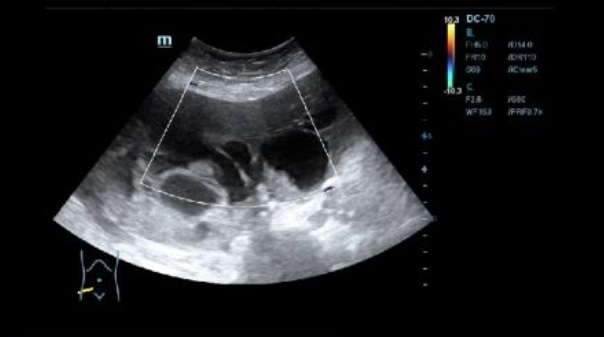

Ecografía: se observa presencia de líquido ascítico, e imagenes en hipomesogastrio hipo e hiper ecogénicas, tabicadas algunas, con efecto masa, con vascularizacion al Doppler que sugieren carcinoma de ovario.

Neoplasia de ovario bilateral con carcinomatosis peritoneal y omental, implantes peritoneales y subcapsulares hepáticas y abundante ascitis.